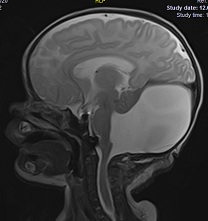

МРТ снимки мальформации Денди-Уокера